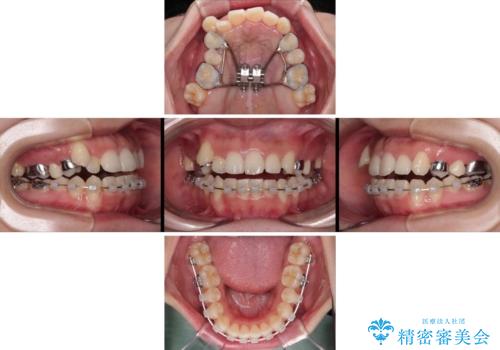

上顎の急速拡大装置を使用して上顎骨を側方に拡大することで上顎歯列を拡大し、下顎歯列も拡大できるようにすることで、歯列を整えることとしました。

歯列矯正では基本的に骨格を改善することはできませんが、急速拡大装置(MARPE)を使用することで上顎骨を側方に拡大させることができ、咬合状態を大きく改善することができます。